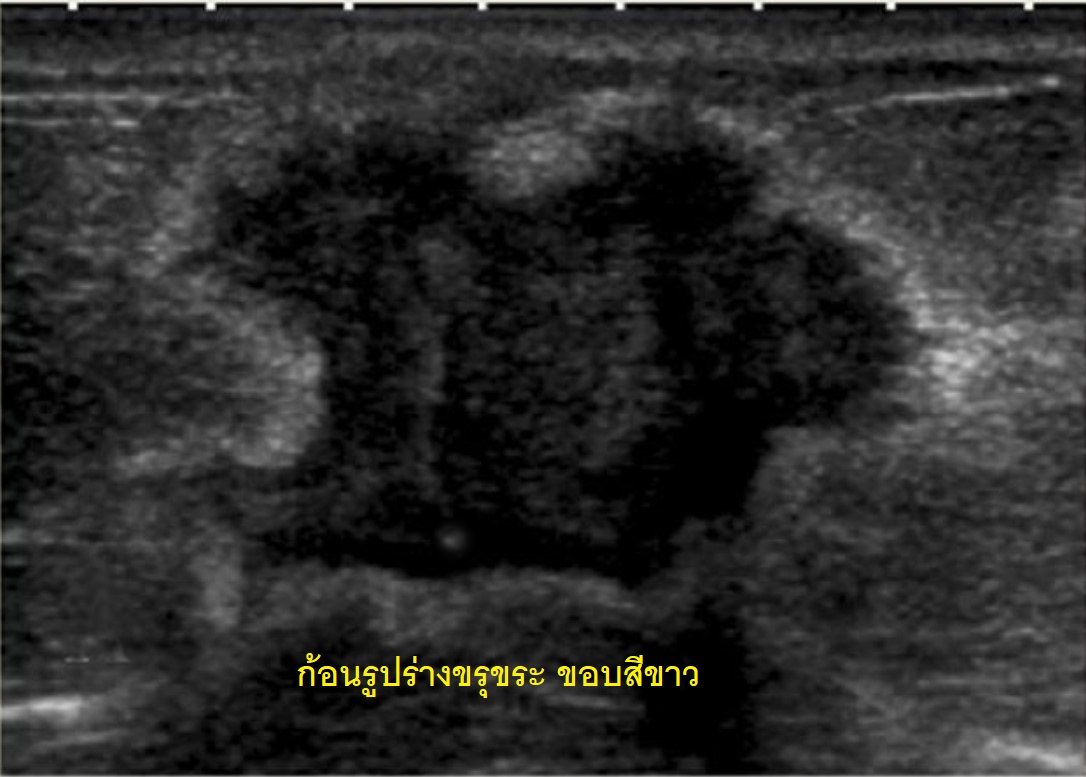

ก้อนขรุขระ

(Irregular mass)

ภาพอัลตร้าซาวด์แสดงให้เห็นก้อนมีรูปร่างขรุขระ

ขอบขรุขระ ด้านนอกก้อนมีสีขาวหนาล้อมรอบขอบก้อน

ลักษณะเช่นนี้มีความเหมือนโรคมะเร็งได้สูงมาก

จึงต้องรีบเจาะเก็บเนื้อเยื่อจากก้อนส่งพิสูจน์มะเร็ง